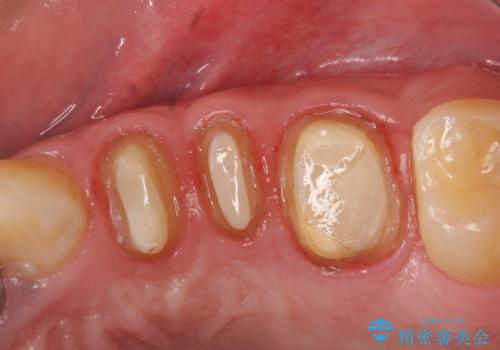

- 左上奥歯の銀歯をセラミックにしたいといらっしゃった方の症例です。

銀歯を除去したところ歯茎よりも深い位置まで虫歯があったため、歯冠長延長術(歯周外科)を行いました。

その後歯茎の回復を待つ間に再根管治療を行い、歯茎の回復後オールセラミッククラウンにて補綴を行いました。